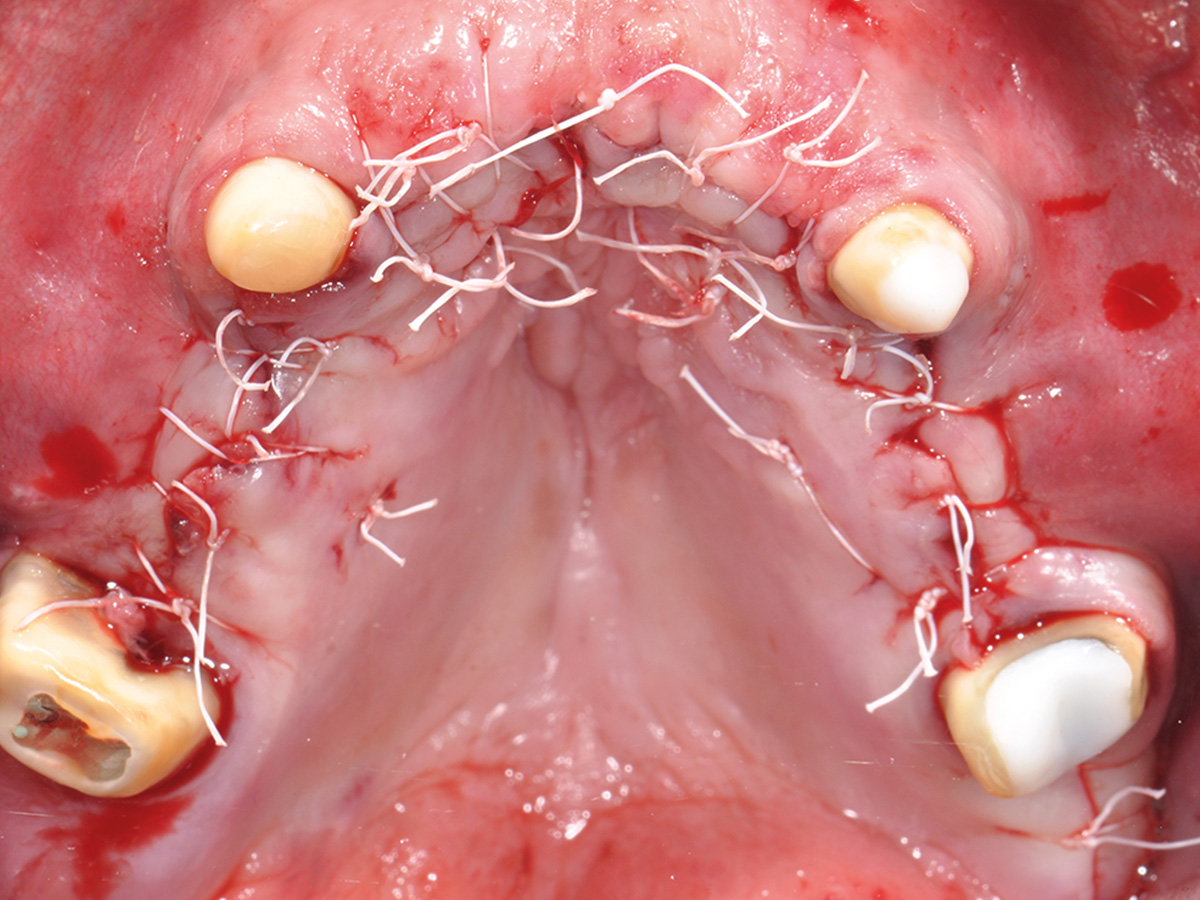

Im Anschluss werden am Tiermodell alle für eine vorhersehbare Augmentation notwendigen Techniken im Sinne des „Simplify your Augmentation“ eingeübt. Der Weg führt von der einfachen Membrananwendung über die Bone-Lamina- und Double-Layer-Technik bis zur Bone-Shield-Technik. Das Bone Shield ist eine Evolution der klassischen Schalentechnik und erlaubt es, auch komplexe vertikale und kombinierte Augmentationsfälle

im Rahmen der im Kurs vorgestellten Konzeption sicher zu lösen.